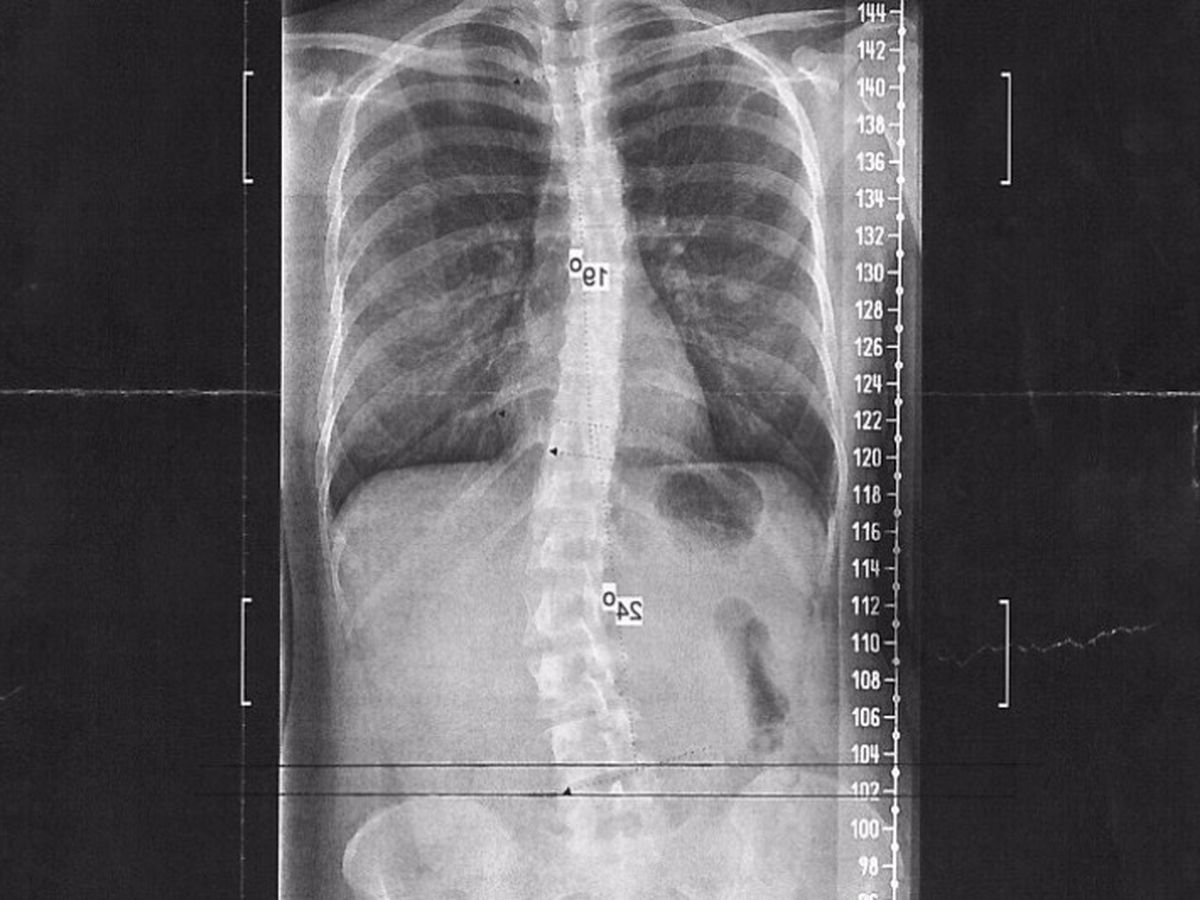

I was first diagnosed with scoliosis when I was about 11. Everybody has one leg shorter than the other, but mine is offset by a whole centimeter. The doctor didn't attempt to treat it, but opted to"wait and see." Waiting has left me with a 19 and 24 degree curvature. My scoliosis holds me back in a lot of ways (pun intended). I've thrown my back out several times since I was 19. Almost everyday, I have a tightness in pain somewhere be it my neck, upper, or lower back. Holding correct posture for me isn't just challenging, it's painful. Exercise tends to make it worse. I also get winded easily, especially when I do core exercises, which is frustrating, because core muscles are the most important to exercise in dealing with scoliosis. Basically, I'm dealing with chronic pain syndrome, which leads to chronic fatigue, and some research suggests chronic anxiety.